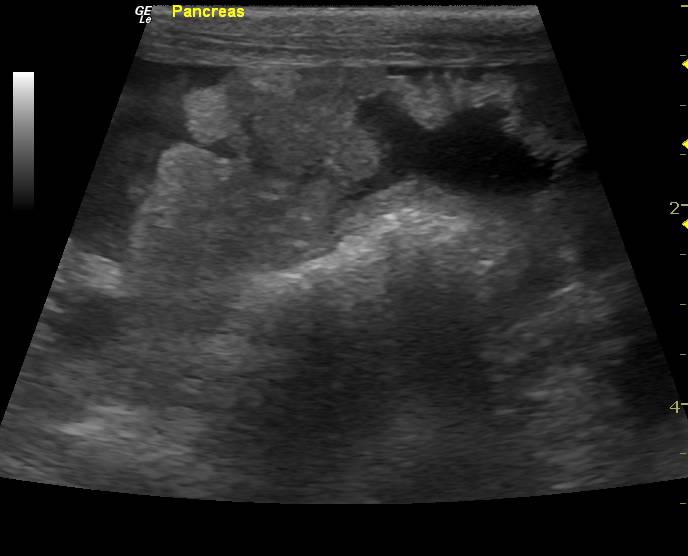

The abdomen in this patient presented moderate amount of echogenic free fluid. Multiple heterogenous nodular changes were noted which were hypoechoic and hyperechoic throughout the liver. This is suggestive for metastatic event. Some internal structure deviation was noted. The deep right liver revealed a collapsed gallbladder with surrounding parenchymal nodular changes with impingement upon the gallbladder. The vena cava was normal. The hepatic veins were subnormal in size. This is indicative of an increased possibility of feline infectious peritonitis. The pancreatic region revealed multiple nodular hypoechoic changes with irregular surrounding omentum.

Bi-cavitary effusion. Nodular pancreatic and hepatic changes. This is highly suggestive for dual cavity neoplasia such as carcinomatosis or possible feline infectious peritonitis. An abdominocentesis with cytospin and immediate slide preparation would be recommended for a definitive diagnosis. Alternatively, fine-needle aspirates of the pancreas and liver nodules would be warranted. Very poor long term prognosis.

Pancreas: carcinoma. Liver: carcinoma (suspected metastatic).

FNA of liver revealed carcinoma (suspected metastatic). FNA of pancreas: carcinoma. Comments: Given the appearance of the slides as well as the sonographic description, the pancreas is likely the site of primary neoplasia, with metastases to the liver. The neoplastic cells appear epithelial but do not contain zymogen granules typical of normal pancreatic cells. This could be because the cells are sufficiently anaplastic as to have lost this feature, but other sources should be considered as well.